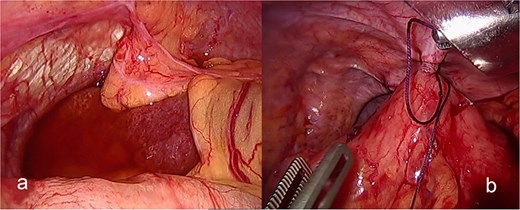

The patient was admitted under the care of the general surgery department, and he was taken to the operating room for a laparoscopic exploration, which showed mesenteroaxial gastric volvulus, wandering spleen, and a large hiatal hernia which was ~5 cm in size. No devitalized tissues were found. An attempt at intraoperative endoscopy failed to pass through the hiatus. A cruroplasty with a Toupet fundoplication and gastropexy were done as shown in (Figs 3 and 4). On the third postoperative day, the patient was doing well. He was tolerating oral intake and passing regular motions and was discharged home in good condition as he was traveling to his country.

(a) The spleen appears healthy and in an abnormally mobile position, consistent with a wandering spleen, with absent or lax ligamentous attachments. (b) Postreduction view of the stomach, with its body sutured to the lateral abdominal wall (gastropexy) to prevent recurrence of mesenteroaxial gastric volvulus.